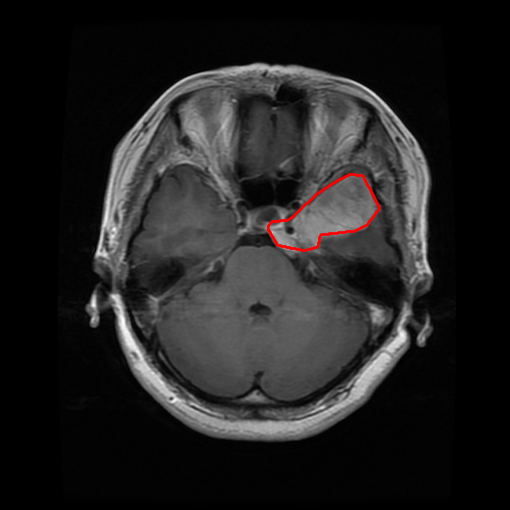

From the above discussions, we have discovered the significant potential of applying Retinex theory to image segmentation and explored its fundamental differences from traditional models. Traditional image segmentation models typically focus on the impact of intensity information on the segmentation results. Therefore, when faced with complex segmentation scenarios, the segmentation results are often affected by lighting, artifacts, and unclear boundaries in the image. As shown in Fig. 1, we present the results of the classical local model LIF [ZHANG20101199] for segmenting brain tumor images along with surrounding tissue edema. The irregular ring-like enhancement caused by the edematous tissue leads to irregular boundaries and low contrast in the images. Consequently, the LIF model can only identify the central necrotic and liquefied regions of the tumor, failing to detect the boundaries and becoming trapped in local minima. In this paper, we draw inspiration from the Retinex theory, which is widely applied in the field of image enhancement. According to Retinex theory, the reflectance component characterizes the intrinsic structural properties of the observed image and preserves texture information independent of illumination variations. By integrating this reflectance component into the level set framework, our model achieves robust segmentation of medical images even under severe intensity inhomogeneity. In addition, a linearized Structural-Prior is proposed to restore intensity consistency and capture local geometric features, thereby improving boundary localization in complex or blurred regions. Furthermore, a relaxed binary level set representation is employed to enhance robustness against noise and to enable accurate tracking of complex contours. Based on these innovations, we propose a novel variational reflectance-based level set model (RefLSM) that simultaneously corrects bias fields and performs segmentation. Experimental results demonstrate that RefLSM significantly outperforms conventional level set methods in both segmentation accuracy and robustness. We present the results of our model segmenting the two brain tumor images mentioned above in Fig. 2.

To address the challenge of segmenting images with severe intensity inhomogeneity, we propose a linearized structural prior that directly operates on the reflectance component . Reflectance-based structural information is more robust to illumination variations and bias field distortions, helping preserve weak edges and subtle anatomical boundaries. As shown in Fig. 2, our method can accurately delineate tumor boundaries and surrounding edema even under severe inhomogeneity, where traditional intensity-based models often fail. The proposed prior aligns smoothed reflectance gradients with data-driven directions, enhancing inter-region contrast, preserving weak edges, and stabilizing the evolution of . Formally, we define the linear structure operator as the gradient field of the smoothed reflectance: